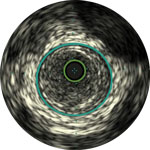

The Visions PV .035 digital IVUS catheter with 60mm imaging diameter evaluates vascular morphology in blood vessels and provides cross-sectional imaging of these vessels.

A practical overview highlighting the value of IVUS in venous, aortic and PAD procedures.

Angiography provides information on luminal characteristics of peripheral arteries, but severely underestimates the extent of atherosclerosis in patients with PAD, even in “normal appearing” vessels.1

Dr Michael Lichtenberg and Dr Konstantinos Stavroulakis discuss the basics of IVUS image interpretation for PAD intervention. Using case- based examples, they demonstrate the added value of IVUS to assess the architecture and pathology of diseased arteries and how this additional information may influence treatment strategy and improve patient outcomes